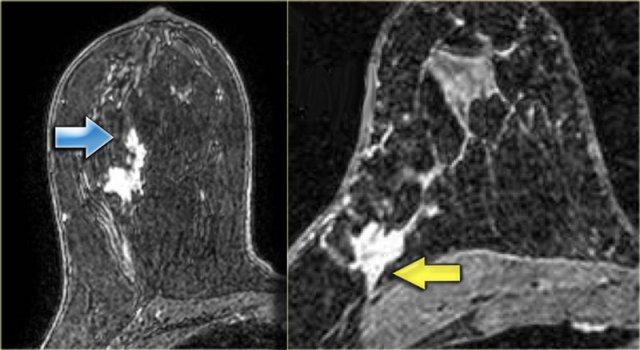

Hình ảnh bên trái cho thấy một khối ngấm thuốc ở vú trái.

Đây được xác định là ung thư xâm lấn.

Phía ngoài khối là một vùng ngấm thuốc không tạo khối theo ống tuyến, được xác định là DCIS.

Hình ảnh ngoài cùng bên trái cho thấy một khối bất thường có lan rộng theo ống tuyến, và

bên phải là một khối bất thường lan đến thành ngực nhưng không xâm lấn vào thành ngực.

Không có ngấm thuốc ở thành ngực.